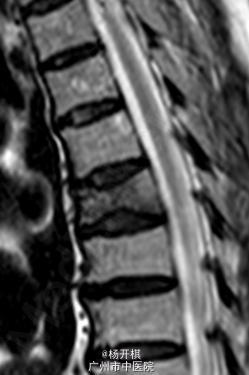

主诉:胸背部疼痛5天。 病史:老年男性,68岁。5天前在起床时突然出现胸背部剧烈疼痛,呼吸稍促,到急诊做心电图及BNP等排除心肌梗死,胸部X线示:T7压缩性骨折。建议患者入院治疗,患者拒绝,回家服药治疗。今日再次门诊就诊,疼痛严重,影响睡眠,影响活动等。患者一般情况较差。

查体:脊柱生理弯曲存在,无明显侧后凸畸形。胸12、腰1-3棘突、棘间及棘旁压痛、叩击痛,余腰、骶棘间及棘旁无明显压痛或击痛。双侧坐骨神经出口处无压痛。四肢肌张力正常,四肢感觉、肌力无明显异常。双侧膝反射及踝反射正常,双侧踝阵挛阴性。双侧Babinski 征及Oppenheim 征(-)。双侧直腿抬高试验(-),加强(-)。 辅助检查:三大常规、血生化、肝肾功能均未见明显异常。患者胸椎动力位片正常,其余重要胸椎影像学如下。

诊断:胸椎压缩性骨折(T7)。 处理:患者入院后完善相关检查,并给予对症治疗,科里术前讨论决定:拟行手术:T7经皮椎体成形术。